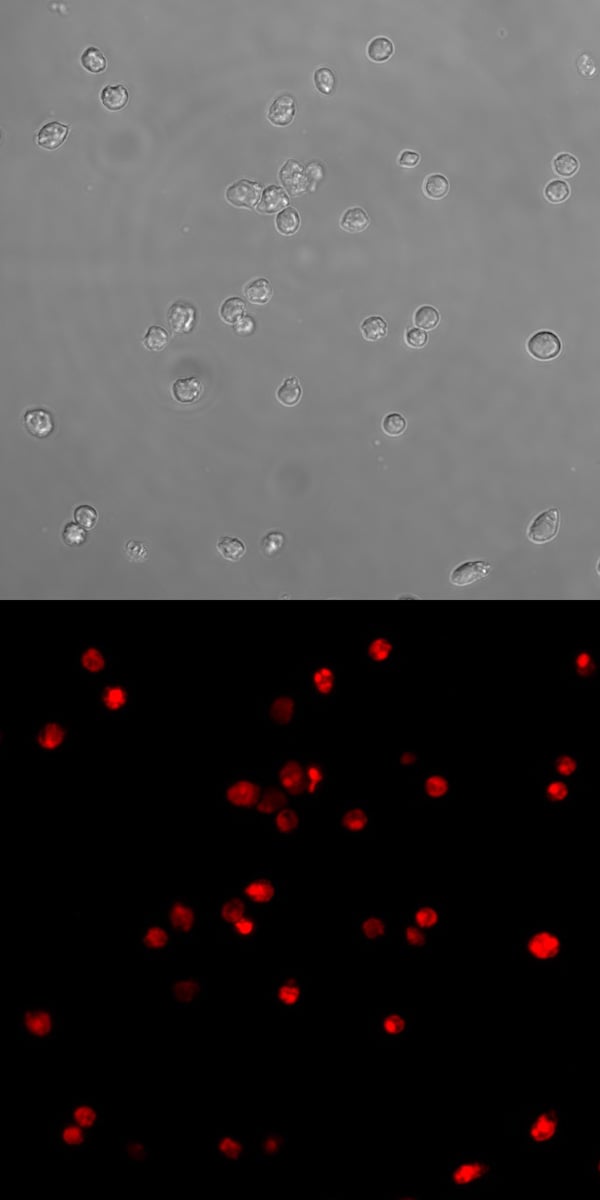

(Jurkat cells were treated with 1 uM staurosporine toinduce caspase 9 activity (left), or a negative control(right) for 3 hours, washed twice, then incubated withICT's red caspase 9 inhibitor probe, SR-LEHD-FMK, for 1hour and examined under a fluorescence microscope.DIC images were also taken of all cells. Both inducedimages reveal several experimental cells which fluorescered, therefore they have some degree of caspase 9activity. The non-induced DIC image reveals many controlcells, however the corresponding fluorescence image isdark; none of these cells have active caspase 9 (Dr. BrianW. Lee, ICT).)